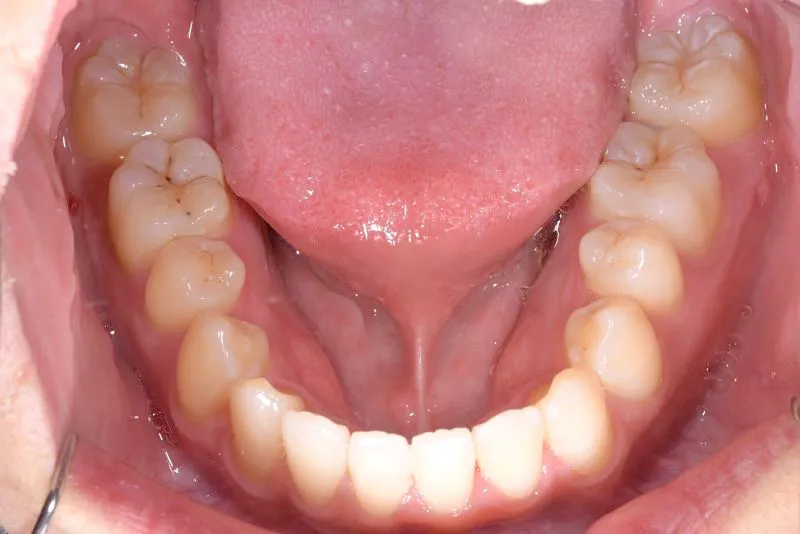

【大人の矯正】叢生・八重歯・交叉咬合・非抜歯症例・19歳女性【R.T様】

初診時年齢 19~29歳 (女性) 主訴 ガタガタ・交叉咬合が気になる

診断名 叢生・交叉咬合 装置名

ガタガタ・八重歯を主訴に来院された患者様です。

初診